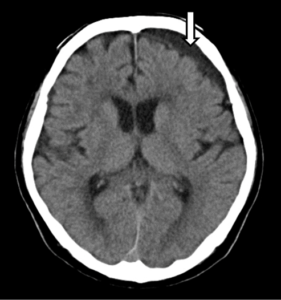

Figure 1. 左の慢性硬膜下血腫を呈した入院13日後の頭部CT